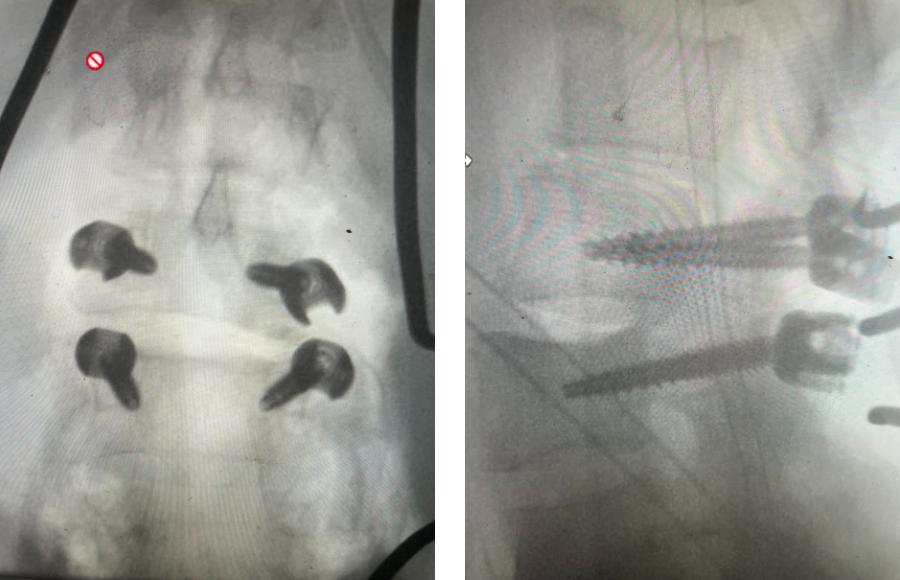

Figure 1: Axial lumbar spine images demonstrating the descent of the nerve root below the subarticular recess as it rounds the pedicle and enters the neural foramen. On the left shows the normal anatomy and on the right showing the descending nerve root being compressed in the lateral recess by a hypertrophied superior process with medial protrusion.

Figure 2: Cartoon axial image of the lumbar spine showing (arrow) severe narrowing of the lateral recess with flattening of the nerve root compared to a normal nerve root on the opposite side.

Figure 3: Axial lumbar CT image demonstrating severely narrowed left lateral recess by a significantly hypertrophied facet joint (arrow) The lateral recess is formed by a triangle of the superior facet process, the pedicle, and the anterior margin of the vertebral body. Note the prominence and anterior protrusion of the superior facet process which is more anterior and medially oriented than the inferior process that comprises the facet joint.